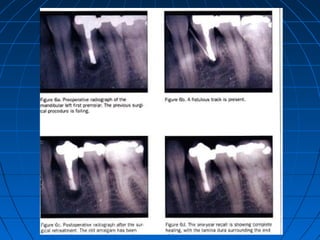

PREOPERATIVE RADIOGRAPH

PLACEMENT OF MTA

REDUCED PROBING DEPTH AT 1-MONTH

HEALED LESION AT 6-MONTH